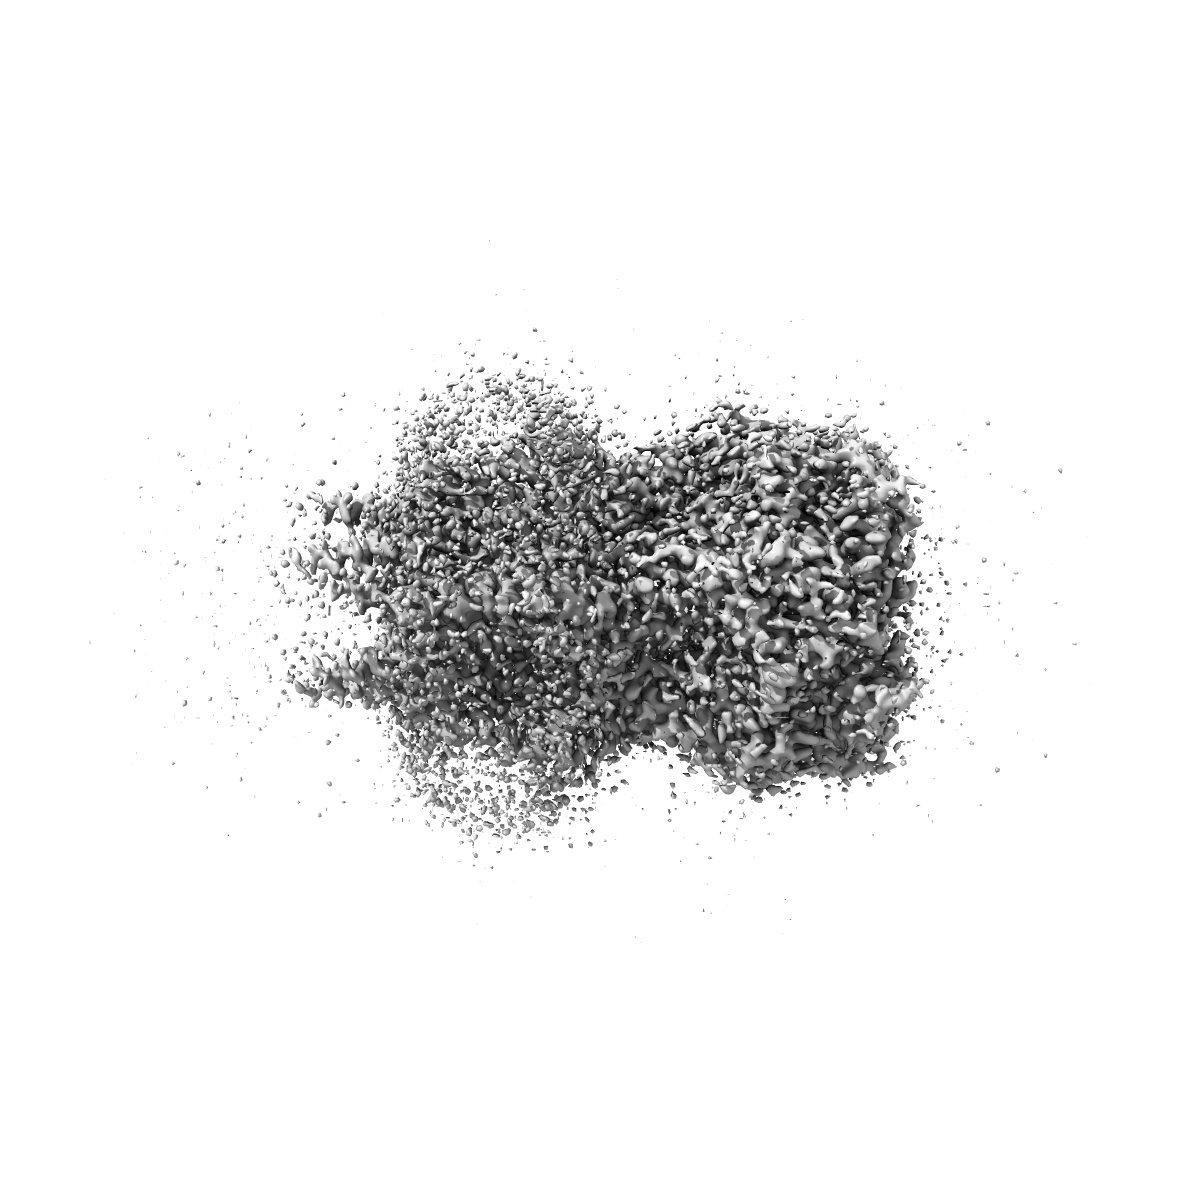

CryoEM structure of human rho1 GABAA receptor in complex with (R)-GABOB in the desensitized state

Sample: human rho1 GABAA receptor

Cryo-EM structures of rho 1 GABA A receptors with antagonist and agonist drugs.

Fan C , Cowgill J , Howard RJ , Lindahl E

(2025) Nat Commun , 16 , 7077 - 7077